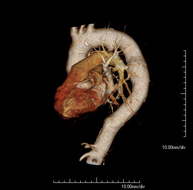

Prova diagnòstica no invasiva que consisteix en l'estudi de l'artèria aorta abdominal a través de l'obtenció d'imatges d'alta definició anatòmica mitjançant l'ús d'un equip de TC (Tomografia Computeritzada) i de contrast iodat. La qualitat de les imatges permet realitzar reconstruccions en 2D i 3D gràcies a estacions de treball especialitzades en l'estudi arterial. Està indicat en aquells pacients amb malaltia vascular (arteriosclerosi), en aneurismes d'aorta, en pacients amb dolor abdominal de possible origen vascular, en estudis prequirúrgics de lesions adjacents a l'aorta abdominal com a "mapa" vascular. La informació obtinguda de manera no invasiva és indispensable per als pacients que requereixen tractament percutani o quirúrgic. En aquells pacients que només requereixen seguiment de les lesions vasculars, aquesta tècnica és la tècnica no invasiva d'elecció juntament amb l'angio-RM. - Angio-TC Artèries renals

Prova diagnòstica no invasiva que consisteix en l'estudi de l'artèria aorta abdominal amb l'obtenció d'imatges d'alta definició anatòmica mitjançant l'ús d'un equip de TC (Tomografia Computaritzada) i contrast iodat. La qualitat de les imatges permet realitzar reconstruccions en 2D i 3D gràcies a estacions de treball especialitzades en l'estudi arterial. Està indicat en aquells pacients que pateixen malaltia vascular (arteriosclerosi), aneurismes d'aorta, en pacient amb dolor abdominal d'un possible origen vascular, en estudis prequirúrgics de lesions adjacents a l'aorta abdominal com el "mapa" vascular, etc. La informació obtinguda de forma no invasiva és indispensable per als pacients que requereixen tractament percutani o quirúrgic. En aquells pacients que només requereixen un seguiment de les lesions vasculars, aquesta tècnica és la tècnica no invasiva d'elecció juntament amb l'angio RM. - Angio TC d'artèries renals